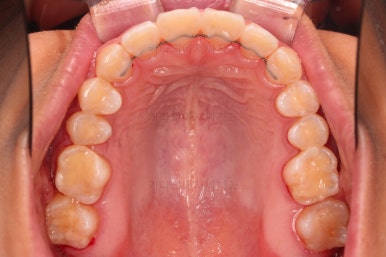

마무리가 잘 되었습니다.

큰 문제는 없었지만, 약간 삐뚤었던 치열이 가지런하게 정렬이 잘 되었고요.

맞물림도 매우 좋고, 뻗친 앞니 각도도 매우 좋아졌습니다.

입 안의 모습만 보면 최상급의 마무리가 되었고요.